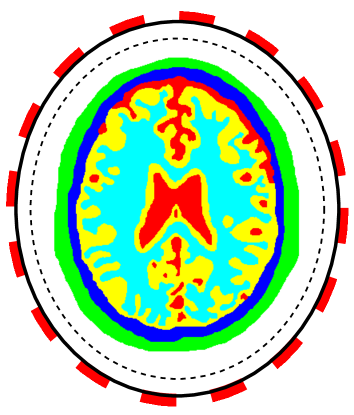

The second example is the human brain model shown in Figure 1(b). The considered tissues in this model include scalp (green, ), skull (blue, ), cerebro-spinal fluid (red, ), gray matter (yellow, ) and white matter (cyan, ). Refer to [5] for conductivities of different tissues. The shape of this model is close to an ellipse whose semi-major and semi-minor axes are and . The model is placed in an ellipse region with a background material (white, ). The semi-minor and semi-major axes of the region are and , respectively. The conductivity maps for the phantoms are piece-wise constant functions which will be mollified with

To work with CEM and LM-SCEM, 16 electrodes (red rectangles shown in Figure 1) are uniformly attached on the boundary (solid black lines). The section occupied by each electrode has the same central angle in both the heart-lung and human-brain models. The following computations assume that the conductivity in a small region close to boundary (between solid and dashed black lines) is known. The distance between the solid and dashed lines is given by . This known region helps to improve the convergence of the algorithm. Three current patterns based on Fourier basis functions are used in the computations, which are for , and . The regularization parameter is chosen to decrease exponentially, and with . In what follows, a relatively large value is given to , and a value close to 1 is given to for a slow decreasing of to ensure the convergence of the iterations.